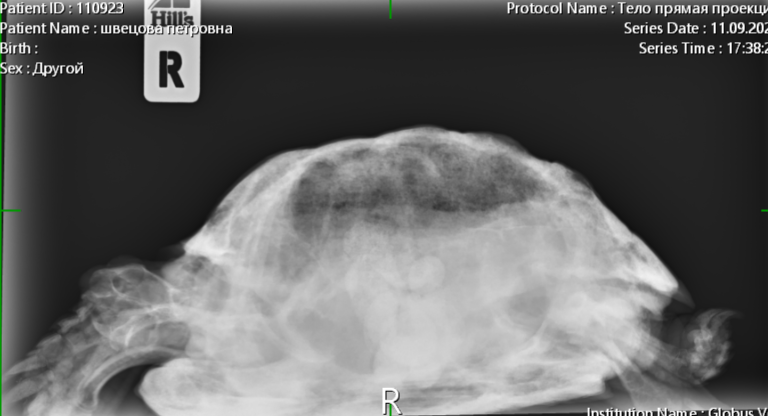

Консультанты moth Ваше имя: Мария Локация: Москва Опубликовано: 7 сентября 2023 Консультанты Опубликовано: 7 сентября 2023 @Алёна.Е. Вам всё в ту же клинику с ней нужно - делать рентген лапы и смотреть что с костями. Если там внутри всё сгнило, то только ампутация. Если нет, то можно пробовать антибиотики. Вы ещё не записывались на приём? Рыбу она поела?

Консультанты moth Ваше имя: Мария Локация: Москва Опубликовано: 8 сентября 2023 Консультанты Опубликовано: 8 сентября 2023 @Алёна.Е. врач ответила, что нужно обязательно рентген. Мускусные черепахи склонны к "гниению" конечностей и скорее всего там гнойный артрит и некроз + сверху бактериальный дерматит. рыбу конечно предлагайте.

Алёна.Е. Ваше имя: Алёна Локация: Пермь Опубликовано: 13 сентября 2023 Автор Опубликовано: 13 сентября 2023 Здравствуйте, были на приёме в клинике 11.09. Рентген сделали, назначили антибиотик, ванны с бетадином и прослушивание. От рыбы также отказывается. Если поможет то лапку попробуем спасти. Фаланги уже рыхлые до локтя. Есть вероятность опухоли, но гисталогию не делали ещё.

Консультанты moth Ваше имя: Мария Локация: Москва Опубликовано: 13 сентября 2023 Консультанты Опубликовано: 13 сентября 2023 @Алёна.Е. а снимков нет на руках? я бы нашему врачу показала, спросить её мнение. Попробуйте предложить улиток, мидий или креветку (желательно сырую) без панциря